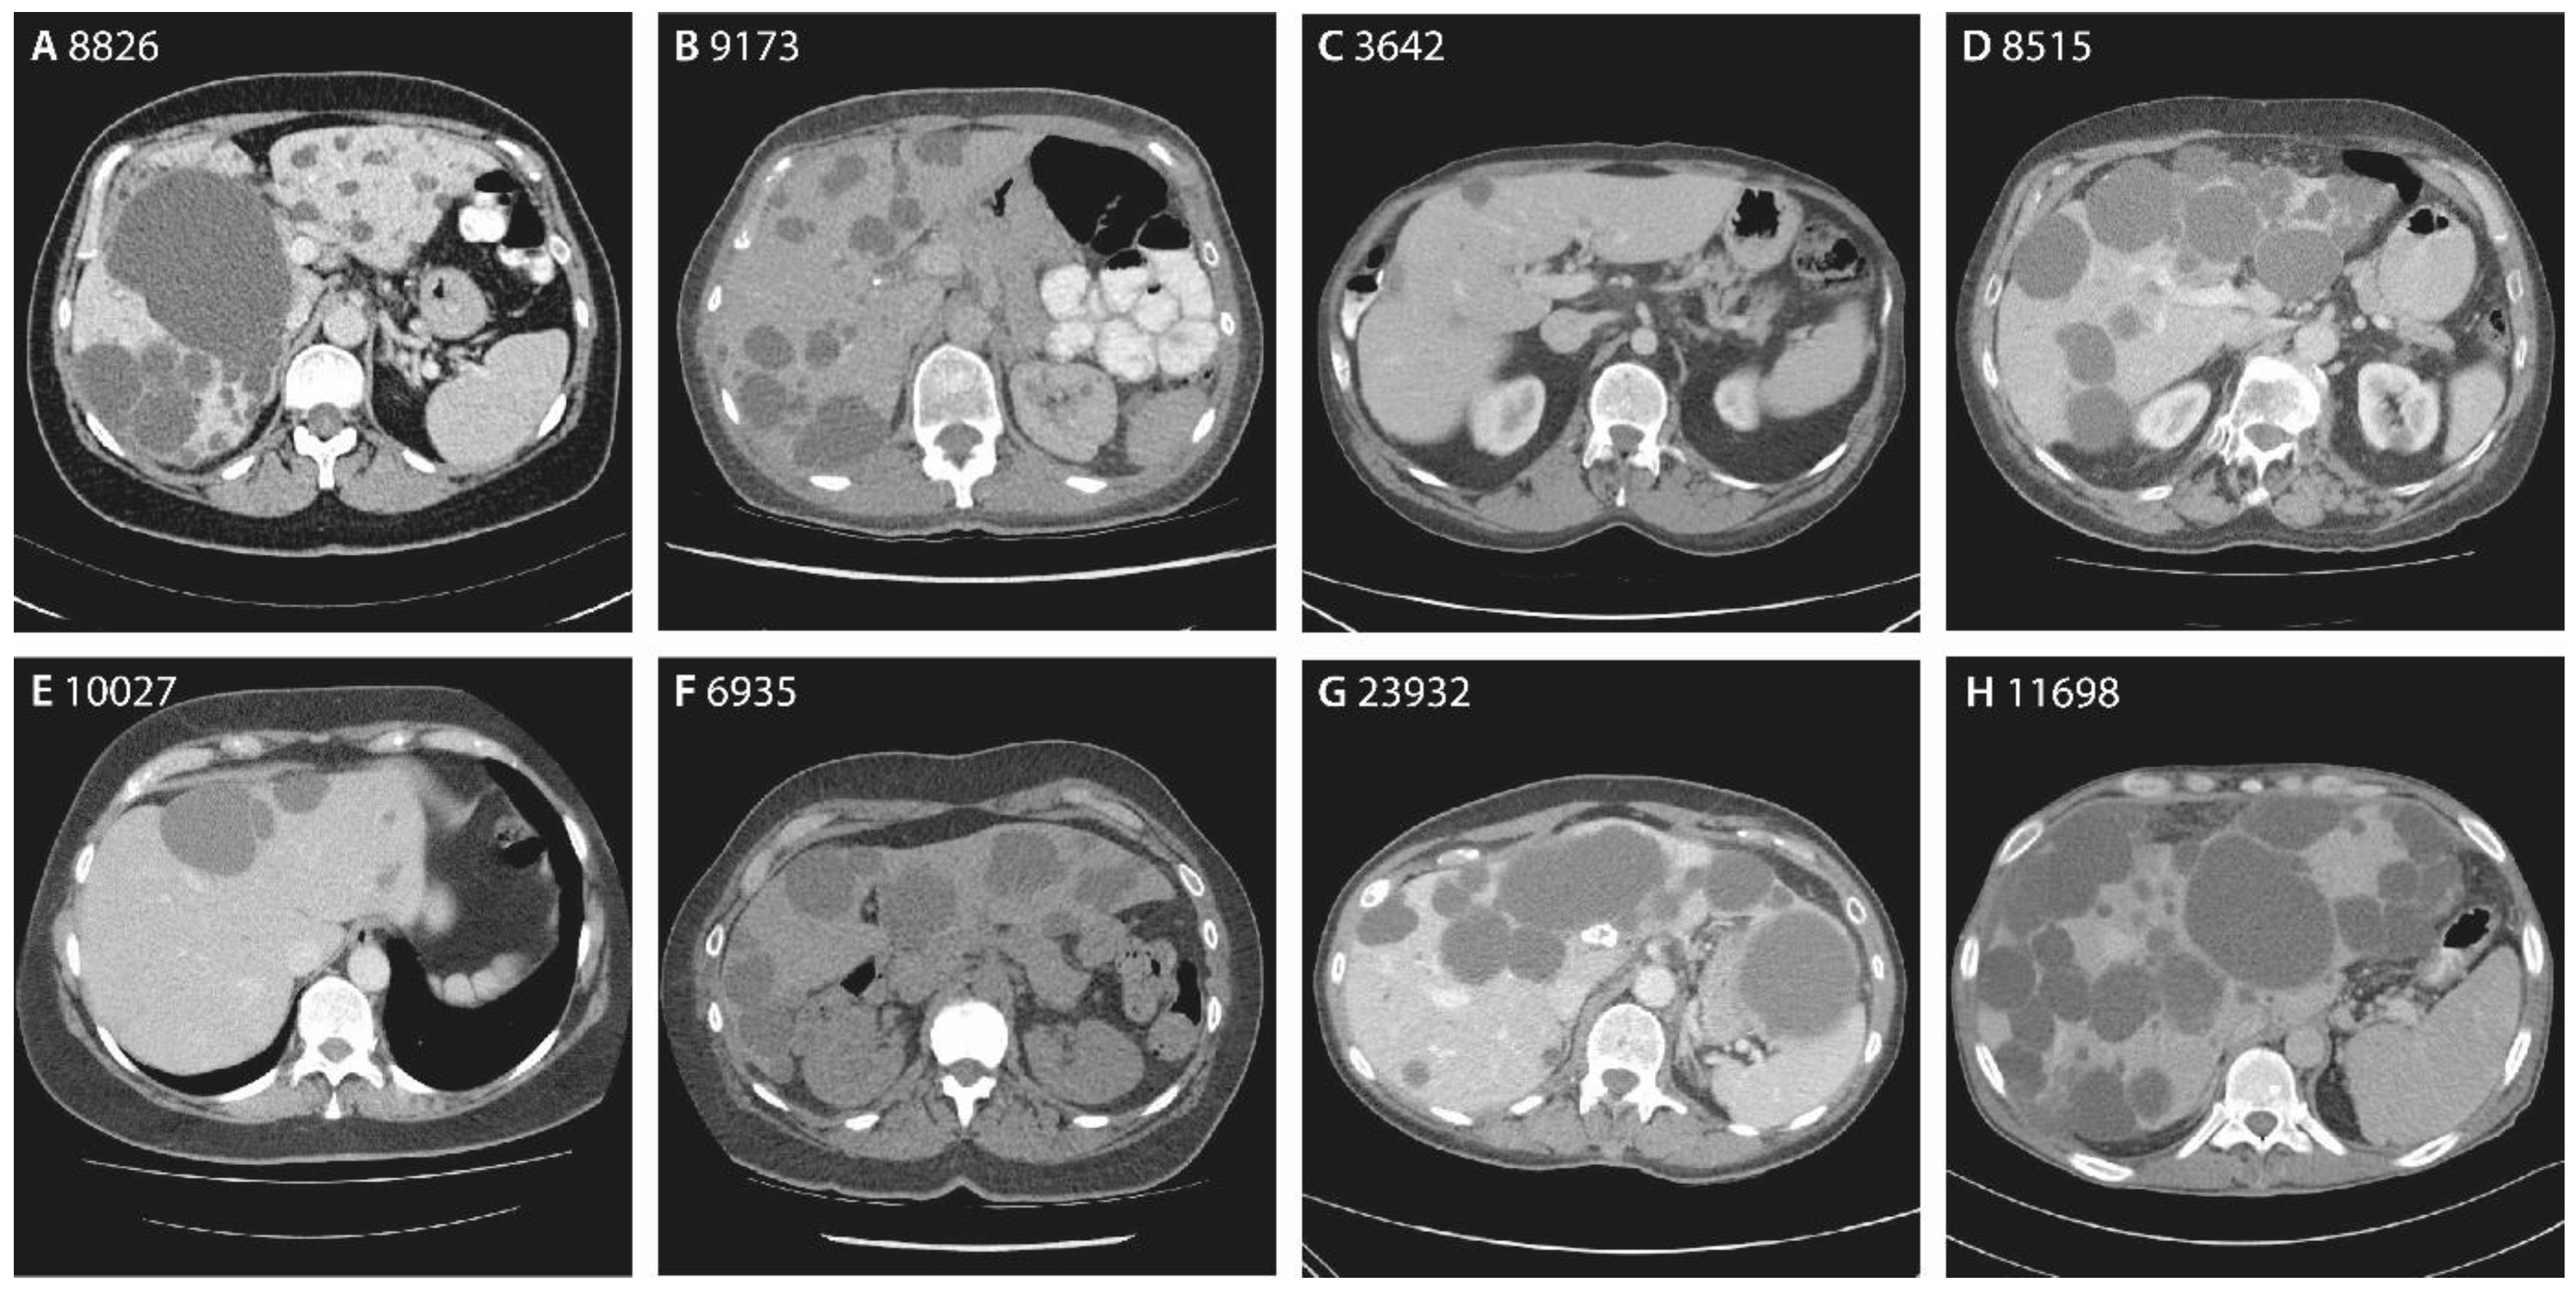

| Chromosome Position | Nucleotide Change | Amino Acid Change | Variant Type | ACMG/AMP | Patient | Sex | Age | Hepatic Cysts | Imaging | GGT | Renal Cysts | eGFR | |

|---|---|---|---|---|---|---|---|---|---|---|---|---|---|

| g.78127372G>A | c.160C>T | p.(Gln54*) | Nonsense | Pathogenic | 9960 | Female | 87 | PLD | US | - | - | - | Family 1 |

| 8826 | Female | 60 | 20+ | CT | 44 | 1 | 69 | ||||||

| 9173 | Female | 44 | 20+ | CT | 15 | 1 | 84 | ||||||

| g.78124118del | c.272delA | p.(Asn91Metfs*5) | Frameshift | VUS | 3642 | Male | 29 | 10+ | CT | 17 | 4 | 89 | |

| g.78121172del | c.371delG | p.(Cys124Serfs*33) | Frameshift | Likely pathogenic | 8515 | Male | 75 | 20+ | CT | 762 a | 1 | >90 | |

| g.78121062T>C | c.478+3A>G | p.? | Splice-site | VUS | 10027 | Female | 56 | 10+ | CT | 29 | 1 | 77 | |

| g.78113978G>A | c.685C>T | p.(Arg229*) | Nonsense | Pathogenic | 6935 | Female | 48 | 20+ | CT | 16 | 0 | 84 | Family 2 |

| g.78109499dup | c.981dupA | p.(Val328Serfs*28) | Frameshift | Pathogenic | 762 | Male | 66 | 5 | CT | 25 | 3 | 79 | |

| g.78106895G>A | c.1090C>T [36,38] | p.(Arg364*) | Nonsense | Pathogenic | 23932 | Female | 59 | 20+ | CT | 410 a | 0 | >90 | |

| g.78101044del | c.1501delG | p.(Val501*) | Nonsense | Likely pathogenic | 11698 | Male | 57 | 20+ | CT | - | 5 | - | |